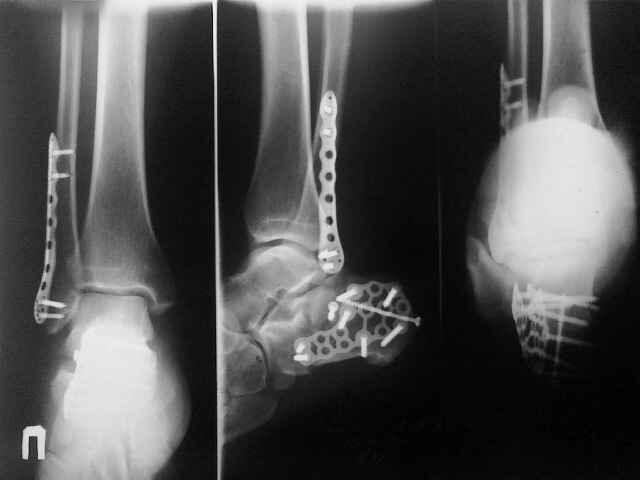

И чем вам не нравится ORIF?... Не нашел первоначальный снимок, но очень похож на представленный. Есть только после операции. Через 6 нед. встал и пошел без боли!